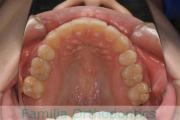

- ≫治療前

上顎

下顎

前歯の関係など

右側

正面

左側